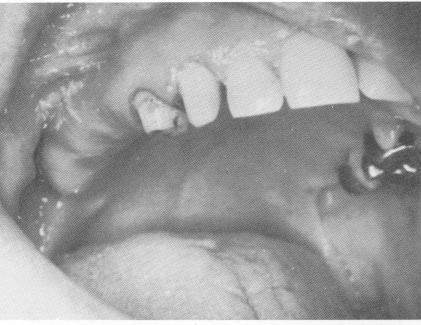

Fig. 11-41. The edentulous site.

1 Edentulous site in maxilla for blade placement